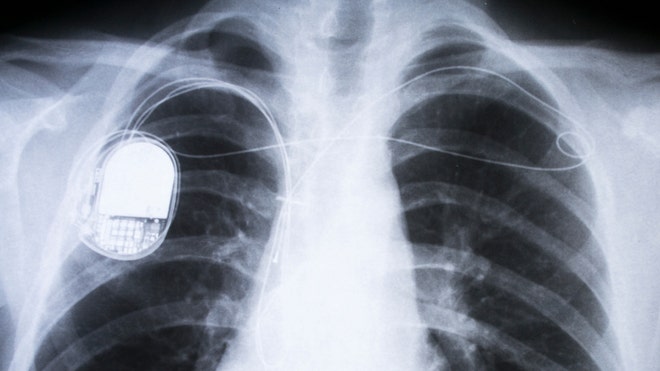

That isn't just fiction, researchers say: Many pacemakers and other implantable medical devices (IMDs), such as insulin pumps, connect to the Internet via Wi-Fi to share important medical data with doctors. But very few of these devices use secure connections.

Although there are no known instances of someone hacking a pacemaker or similar device to harm another person in real life, the danger is real: Security experts have demonstrated for years that hackers could easily steal medical data from IMDs, or even take control of the devices, causing pacemakers to emit shocks, insulin pumps to overdose their wearers, and ventilators to stop working.

Pacemakers

The researchers say their program would work best with pacemakers, but could also be used in any IMD that can reliably detect the pulse.